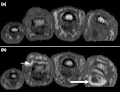

T1-weighted semi-coronal MRI of sacroiliac joints (a) before and (b) after contrast showing active sacroiliitis (arrow). -

Coronal T1-weighted MRI of fingers in PsA. (a) Pre- and (b) post-contrast showing active synovitis at proximal and distal interphalangeal joints (large arrows), joint space narrowing, bone proliferation at proximal interphalangeal joint, erosions at distal interphalangeal joint (white circle), enthesitis medial to proximal interphalangeal joints. -